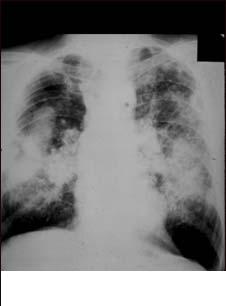

Antracoza sau plamanul negru - pneumoconioza minerului de carbune